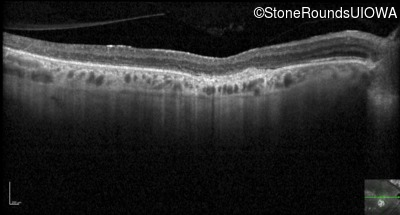

Optical Coherence Tomography - Left - 20/125

Exemplar / OCT Stack

OCT Stack